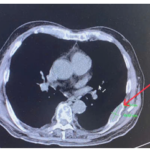

CASE LÂM SÀNG Điều trị bệnh nhân mắc đồng thời hai loại ung thư: Ung thư phổi và ung thư tuyến tiền liệt

CASE LÂM SÀNG Điều trị bệnh nhân mắc đồng thời hai loại ung thư: Ung thư phổi và ung thư...